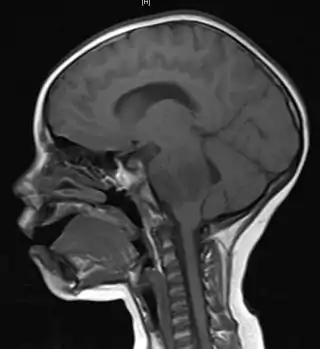

![]() Resonancia magnética sagital en la que se observa un glioma en el tronco cerebral de un paciente de 4 años de edad. | ||